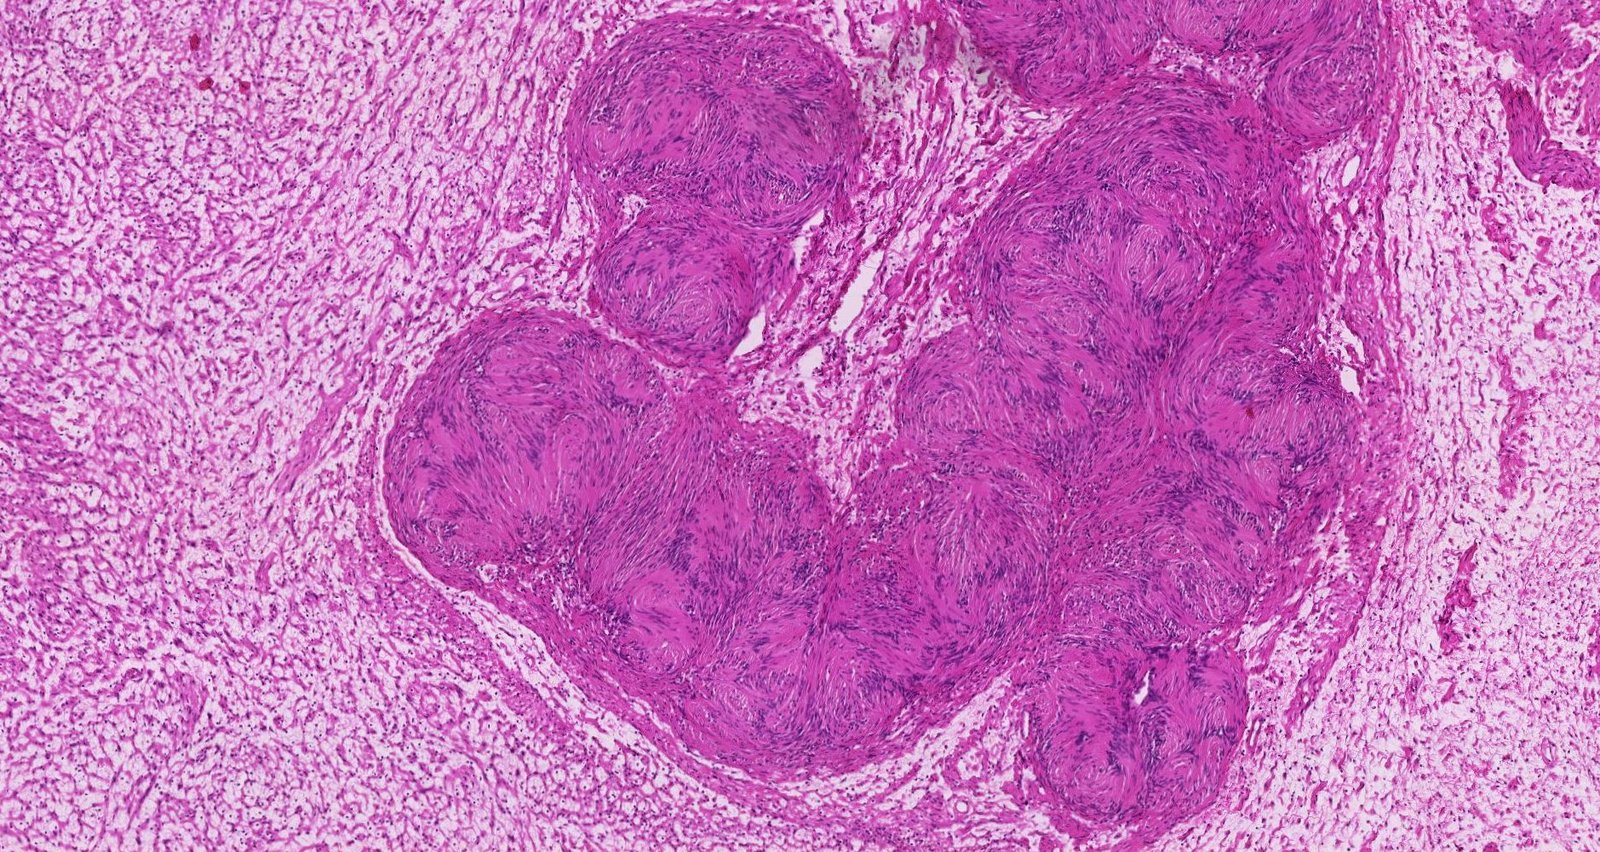

• Gross findings: encapsulated firm mass

• Microscopic findings

• Spindle cells in palisades (Antoni A tissue) alternating with myxoid hypocellular areas (Antoni B tissue)

• S-100 positive